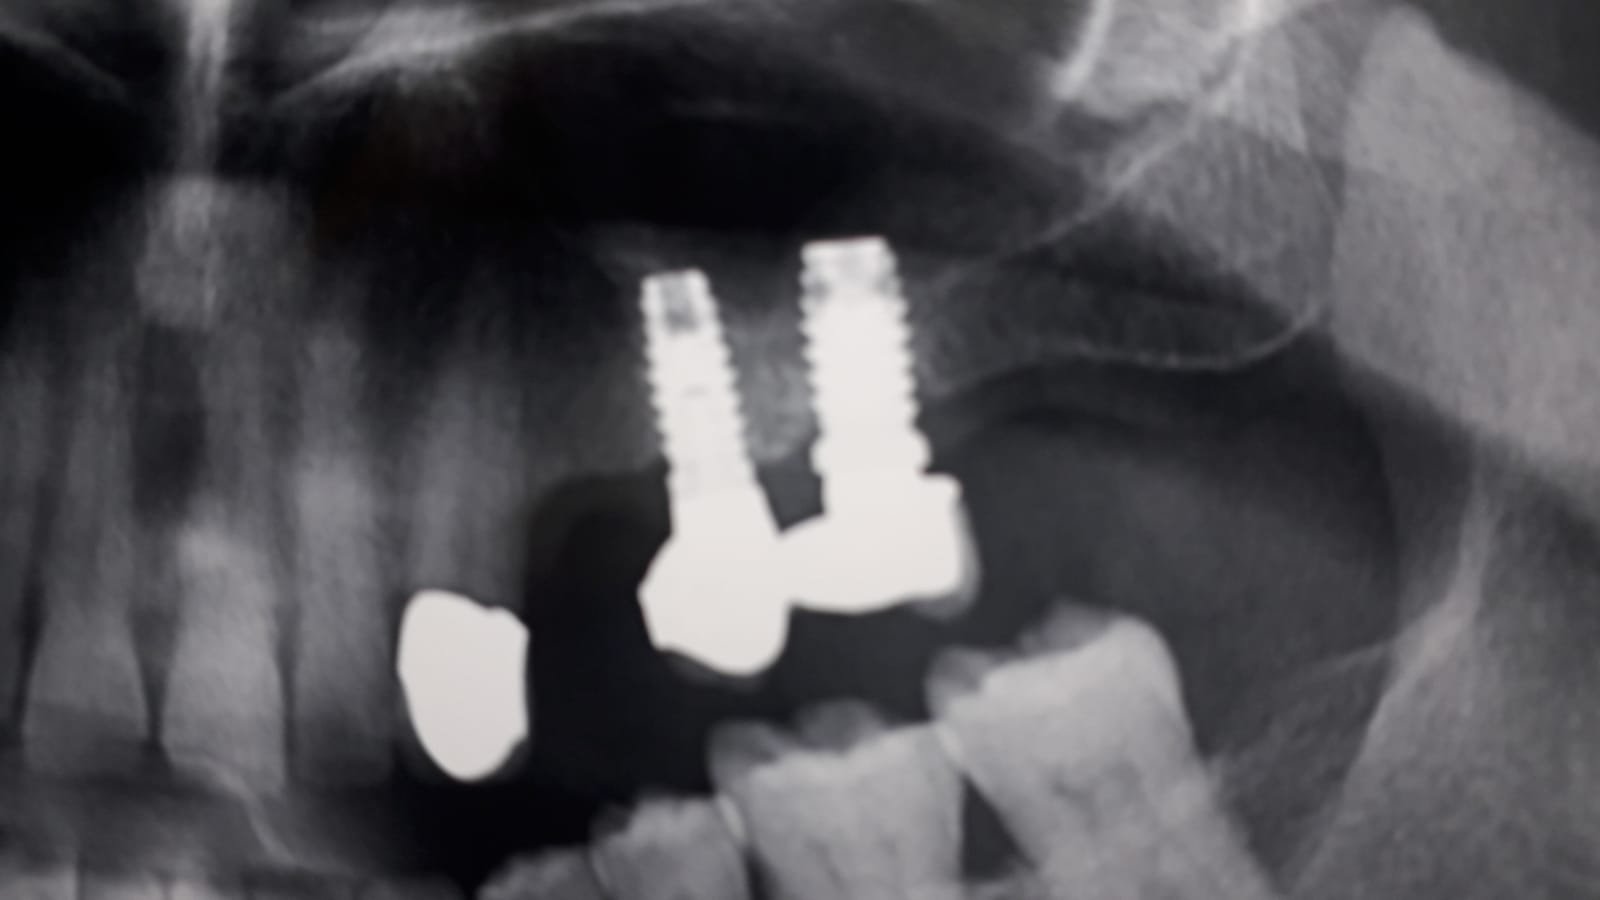

Buenas dias compañeros, saludos a todos tengo a este paciente con unos implantes ajenos en molares y tras haber realizado exo de 15 me gustaría hacerle un nuevo puente con [...]